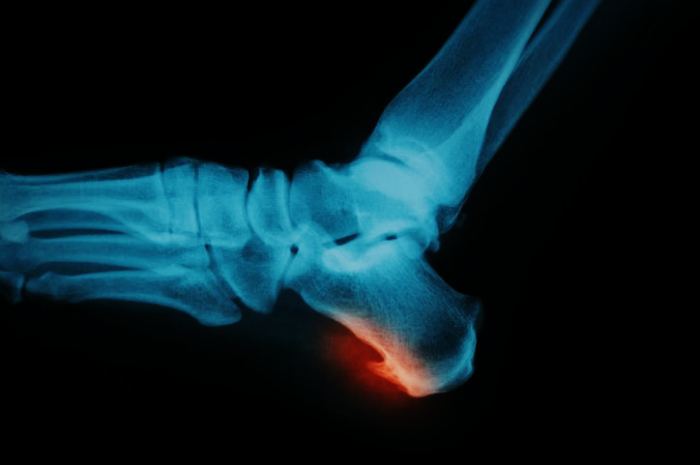

Поставить правильный диагноз на основании жалоб и внешнего осмотра практически не возможно. Так как можно спутать с другими заболеваниями.

Правильной диагностикой будет считаться направление на лабораторные исследования. Это общий и биохимический анализ крови и также мочи. Самым информативным исследованием считается МРТ, оно поможет с точностью определить степень поражения.И также если для пациента это исследование считается дорогим, врач назначает рентген пяточной кости. Только после этих исследований ставится правильный диагноз и назначается лечение.